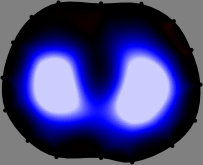

Refer to caption

Figure 2: Fidelity-embedded regularization method. (Left bottom) Correlations between four different column vectors (𝐒ksubscript𝐒𝑘{\bf S}_{k}) and all the remaining column vectors (𝐒subscript𝐒{\bf S}_{\ell}) are visualized. (Right bottom) Performances of the proposed fidelity-embedded regularization method for λ=𝜆\lambda=\infty are shown by numerical simulations.

To explain the FER method, we closely examine the correlations among column vectors of the sensitivity matrix 𝕊𝕊\mathbb{S}, described in Fig. 2. The correlation between 𝐒ksubscript𝐒𝑘{\bf S}_{k} and 𝐒subscript𝐒{\bf S}_{\ell} can be expressed as

for i=1,,16𝑖116i=1,\cdots,16[23]. This shows that the column vector 𝐒ksubscript𝐒𝑘{\bf S}_{k} is like an EEG (electroencephalography) data induced by dipole sources with directions uj,j=1,,16formulae-sequencesubscript𝑢𝑗𝑗116\nabla u_{j},j=1,\cdots,16 at locations ΔksubscriptΔ𝑘\Delta_{k}. Given that two dipole sources at distant locations produce mutually independent data, the correlation between 𝐒ksubscript𝐒𝑘\mathbf{S}_{k} and 𝐒subscript𝐒\mathbf{S}_{\ell} decreases with the distance between ΔksubscriptΔ𝑘\Delta_{k} and ΔsubscriptΔ\Delta_{\ell}. Fig. 2 shows a few images of the correlation 𝐒k,𝐒(|𝐒k||𝐒|)1subscript𝐒𝑘subscript𝐒superscriptsubscript𝐒𝑘subscript𝐒1\left\langle\mathbf{S}_{k},\mathbf{S}_{\ell}\right\rangle(|\mathbf{S}_{k}||\mathbf{S}_{\ell}|)^{-1} as a function of \ell for four different positions ΔksubscriptΔ𝑘\Delta_{k}. The correlation decreases rapidly as the distance increases. In the green regions where the correlation is almost zero, 𝐒subscript𝐒{\bf S}_{\ell} is nearly orthogonal to 𝐒ksubscript𝐒𝑘{\bf S}_{k}.